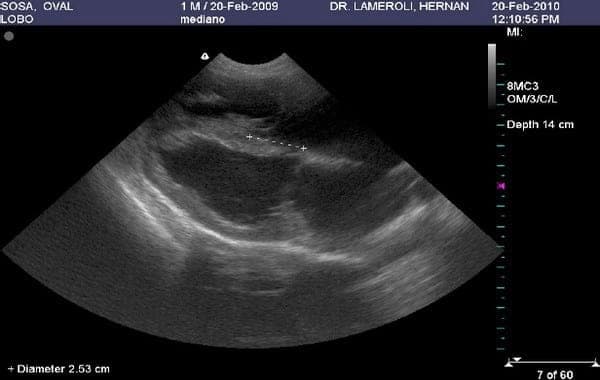

Anomalía de Ebstein en 3 caninos, primer reporte en Argentina - Image 1

Insuficiencia Tricúspide